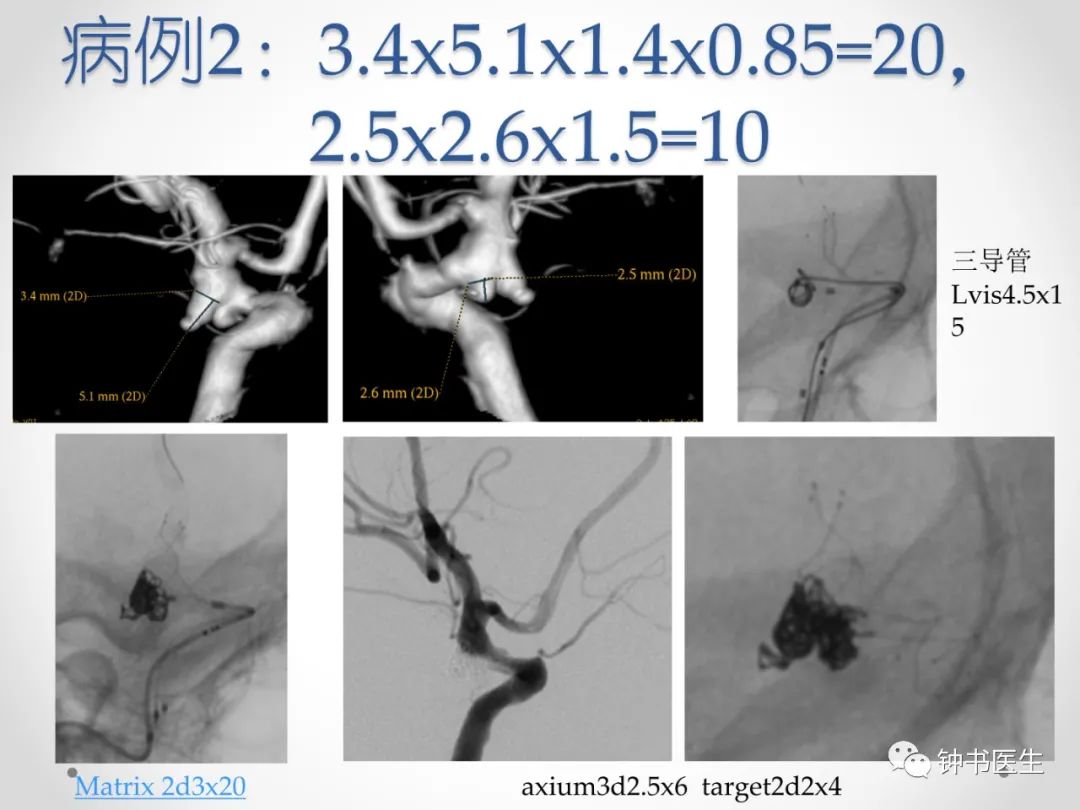

长x宽x1.X=弹簧圈总长度

1.X:X为动脉瘤平均直径

个数:约等于直径(平均直径);

成篮圈直径长度比:4以下2倍;4~7为3倍;7以上大于3倍;取短径加1倍,取长径减1倍!

AXIUM、泰杰、target、galaxy、matrix2、佳奇、微创等

增加0.2 :AXIUM PRIME、Microvention、Visee

减少0.1:GDC、Obit

特殊技术:长圈技术减少15%,大圈技术减少20%